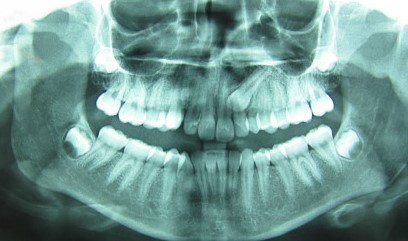

ΟΙ ΚΥΝΟΔΟΝΤΕΣ ΕΙΝΑΙ ΣΗΜΑΝΤΙΚΑ ΔΟΝΤΙΑ. ΓΙΑ ΤΟ ΛΟΓΟ ΑΥΤΟ ΕΓΚΛΕΙΣΤΟΙ ΚΥΝΟΔΟΝΤΕΣ ΣΕ ΝΕΑΡΑ ΑΤΟΜΑ ΑΠΟΚΑΛΥΠΤΟΝΤΑΙ ΧΕΙΡΟΥΡΓΙΚΑ ΚΑΙ ΜΕΤΑΚΙΝΟΥΝΤΑΙ ΜΕ ΟΡΘΟΔΟΝΤΙΚΑ ΜΕΣΑ ΣΤΗ ΣΩΣΤΗ ΘΕΣΗ ΣΤΟΝ ΟΔΟΝΤΙΚΟ ΦΡΑΓΜΟ.

ΧΕΙΡΟΥΡΓΙΚΗ ΑΠΟΚΑΛΥΨΗ ΚΑΙ ΑΜΕΣΗ ΤΟΠΟΘΕΤΗΣΗ BRACKET ΣΕ ΕΓΚΛΕΙΣΤΟ ΚΥΝΟΔΟΝΤΑ ΑΝΩ ΓΝΑΘΟΥ ΣΤΗΝ ΑΡΙΣΤΕΡΗ ΠΛΕΥΡΑ ΤΗΣ ΑΣΘΕΝΟΥΣ.